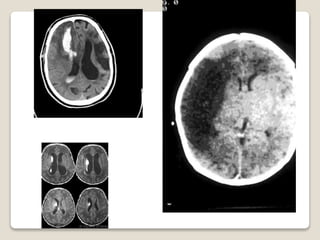

 SISTEMA NERVIOSO CENTRAL

 SISTEMA NERVIOSO – OFTALMOLOGICOS

PATOLOGIA FRECUENTE DELRNPr.  PULMONARES  GASTROINTESTINAL  INMUNOLOGICO  SISTEMA NERVIOSO – OFTALMOLOGICOS  CARDIOVASCULAR  ENDOCRINO